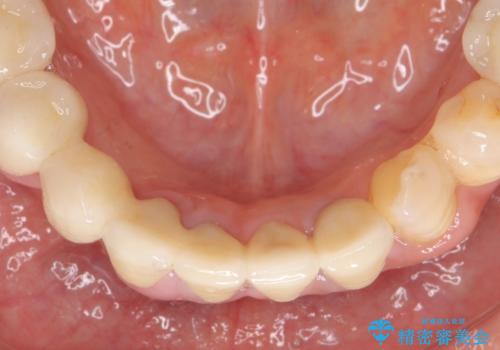

歯周病 全顎治療

失ってしまった機能を回復し、今後歯を失わないよう残せる歯に歯周病治療を行い、安定した咬合を確立することで長期的に問題なく噛めるような口腔内環境を達成できるようになると考えます。